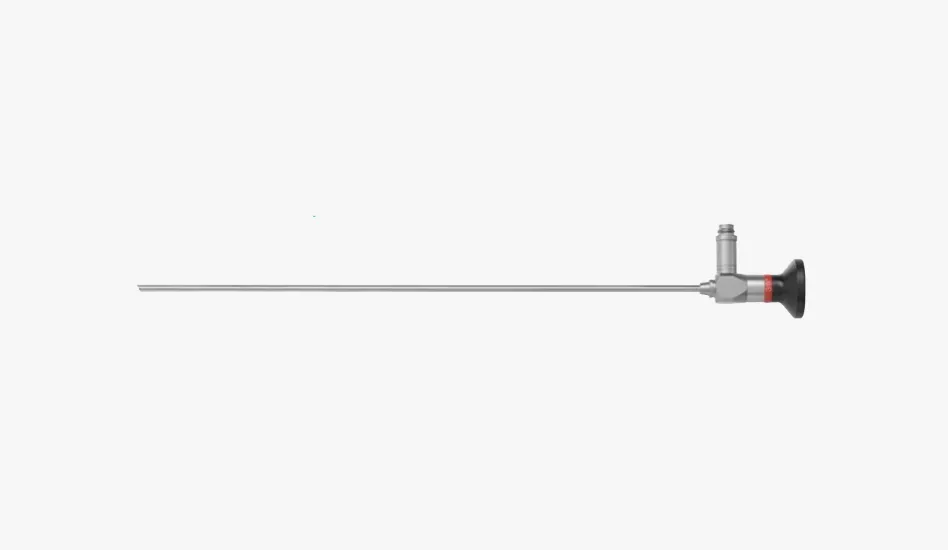

방광 경성 내시경

방광 경성 내시경 -

요관 경성 내시경

요관 경성 내시경 -